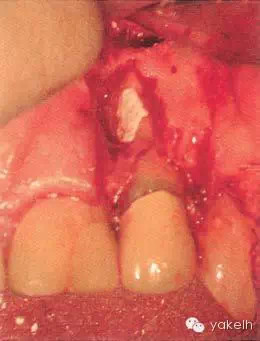

¤¤在征得患者同意后,最終選擇根管外科手術(shù)修復(fù)穿孔。局麻下翻開三角形全厚黏骨膜瓣,充分暴露骨和根面;使用刮匙去除穿孔上覆蓋的肉芽組織,暴露穿孔和樁(圖5.4.2a);使用外科專用渦輪手機(jī)配以金剛砂小球鉆,去除樁的尖端;使用超聲銼去除根管末端的牙膠,并進(jìn)行根管預(yù)備(圖5.4.2b);預(yù)備后的根管與穿孔部位使用IRM嚴(yán)密封閉(圖5.4.2c);瓣復(fù)位、縫合固定,拍攝術(shù)后X線片(圖5.4.3a);3天后拆線。

圖5.4.2(a)去除肉芽組織,暴露穿孔和樁。